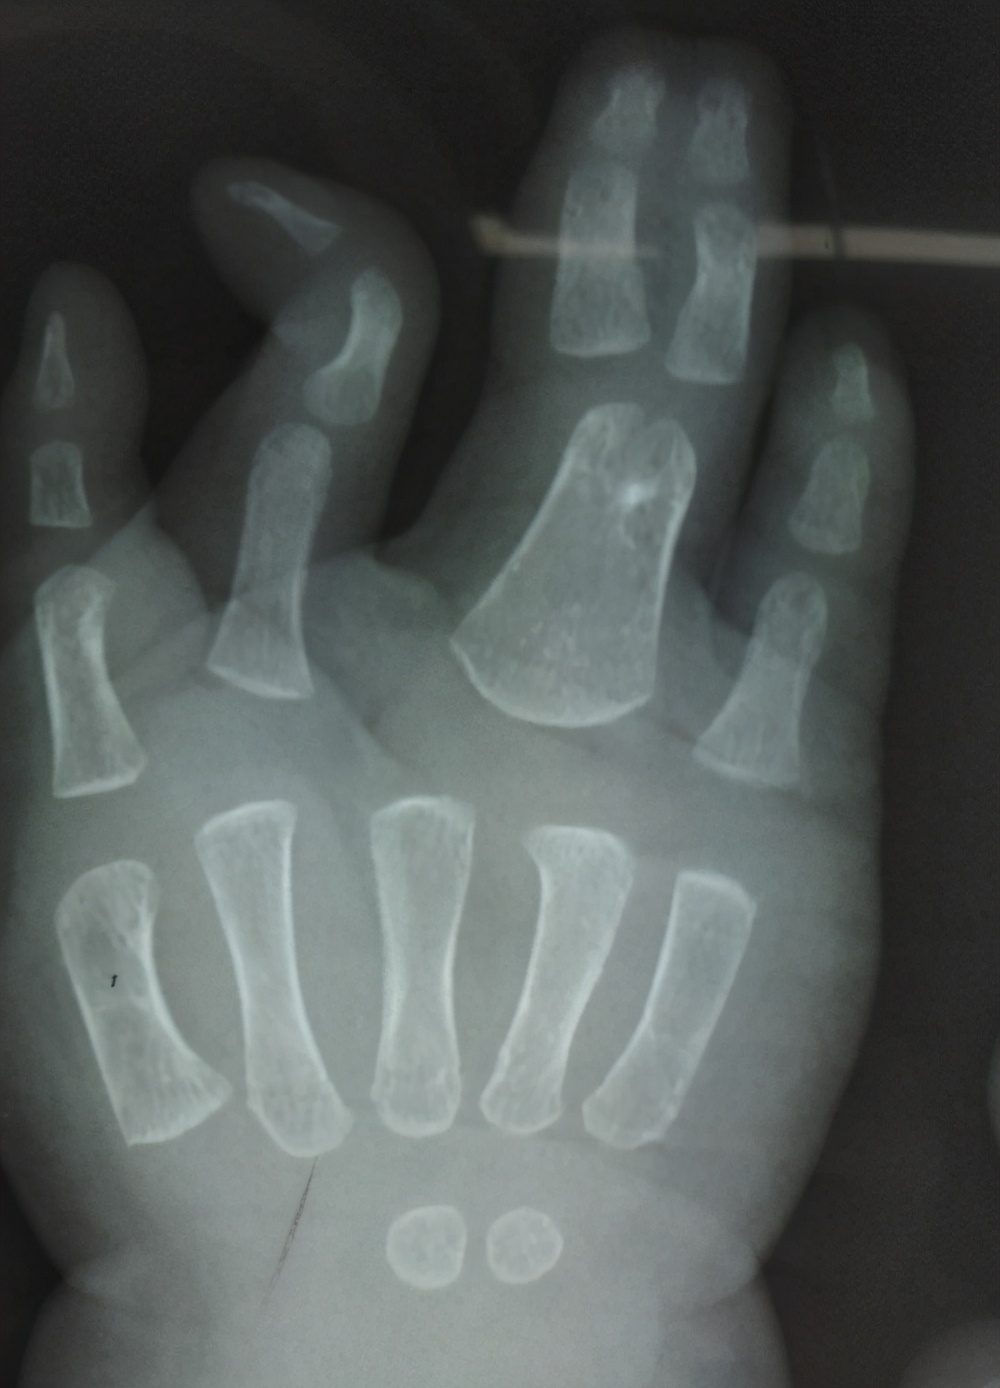

病例7:看到这样的手之后,很多人的第一反应就是怎么只有三根手指,能不能通过手术把三根手指变成五根。其实对于这个孩子的情况,还是要先把并指分开,分开之后可以考虑四根手指,因为通过对比X线片子,我们发现只有三根手指的这个手的第二根手指的指骨和掌骨都比好的那个手指的指骨和掌骨粗,这就意味着这是一个完全的复杂并指。

右手x线

左手x线

如果家长有需求,我们可以给这个孩子进行第二次分指,把三根手指变成四根,分指之后粗细有一定的保障,但是五根手指的可能性不大,哪怕从脚上移植,外观、功能和协调性可能都达不到我们想要的效果,所以四根手指可以探讨,五根意义不大。